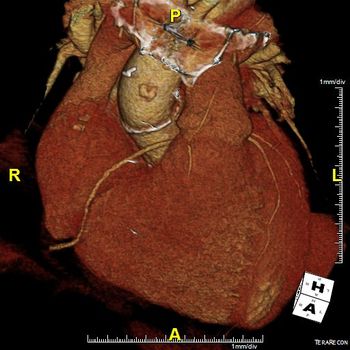

74-year-old with history of aortic valve repair at an outside hospital.